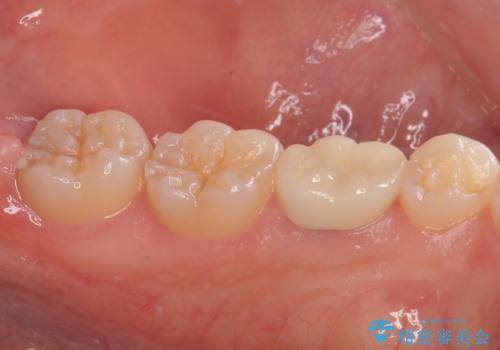

歯と歯茎の間に圧排糸と言われる糸を入れてシリコーン印象材にて型どりをしました。

治療後特に問題もなく見た目、噛み合わせともに満足していただけました。

今後はメンテナンスで通ってもらいながら経過を観察する予定です。